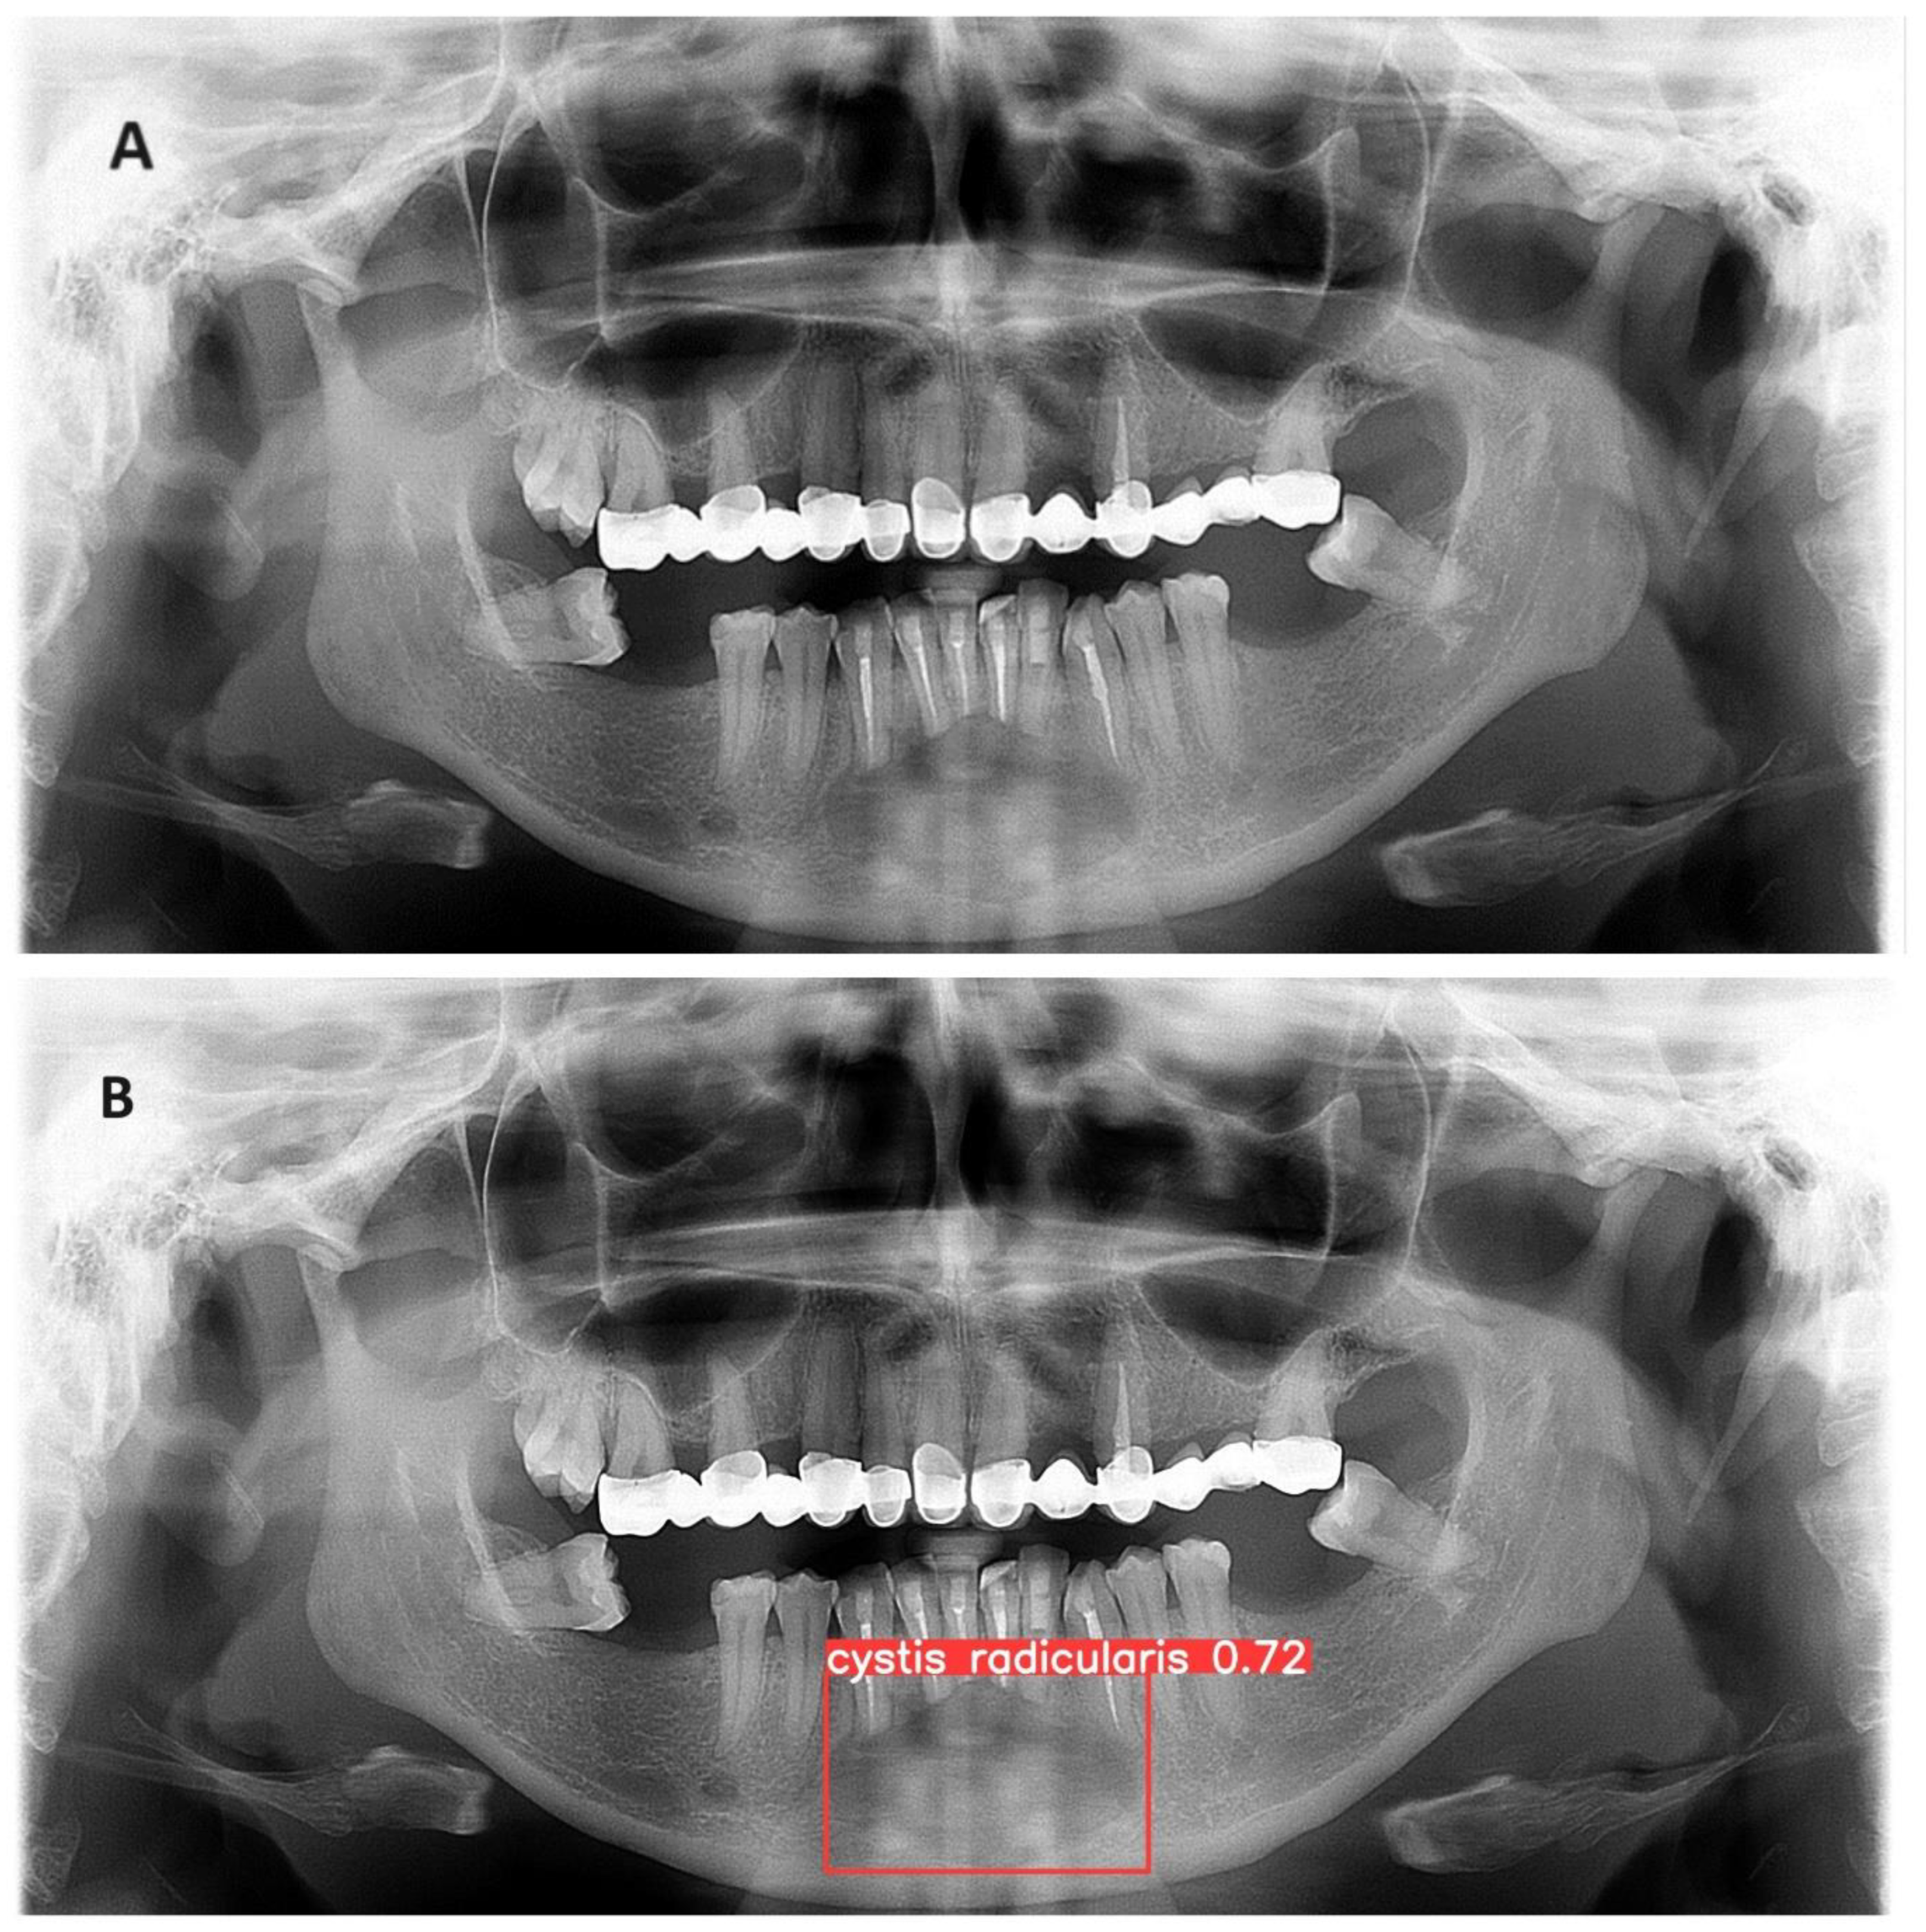

The trained model is capable of predicting bounding boxes and probabilities as shown in Figure 4 and Figure 5.

Figure 4. (A) Panoramic radiograph of radicular cyst in the lower jaw (B) Developed model detection prediction of a radicular cyst with precision of 93%.

Figure 5. (A) Panoramic radiograph of radicular cyst in the lower jaw with surgically removed roots (B) Developed model detection of a radicular with precision of 72%.